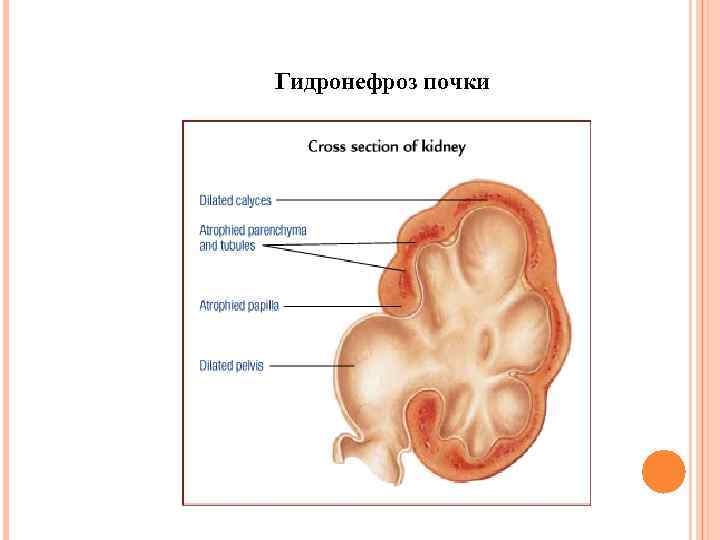

Гидронефроз почки

Гидронефроз почки